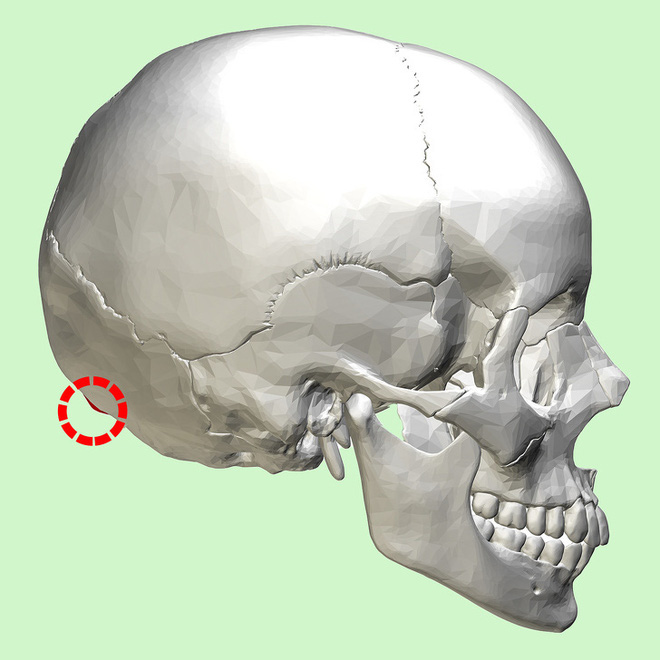

Nó mang tên: Hội chứng... mọc sừng!

Trên thực tế, việc hộp sọ mọc ra những mấu xương với cấu trúc lạ có xảy ra với những người đã qua độ tuổi trung niên. Nhưng theo nghiên cứu của ĐH Sunshine trên hơn 1.200 người trong độ tuổi 18 - 86, thì có đến 1/3 đang xuất hiện mấu xương ở phía sau hộp sọ, với tỷ lệ tăng dần với thanh thiếu niên và người trưởng thành.

Đặc biệt theo nhiều trang tin, các mấu xương này có kết cấu giống như những chiếc sừng, dù không phải sừng. Theo Mark G. L. Sayers - đồng tác giả nghiên cứu, dường như việc này có liên quan đến tần suất sử dụng điện thoại, tablet và các phương tiện điện tử hiện đại khác trong thời gian dài. Tuy nhiên, Sayers cũng cho biết chúng ta vẫn chưa thể kết luận việc dùng điện thoại thực sự là nguyên nhân, mà cần thêm thời gian để khẳng định.